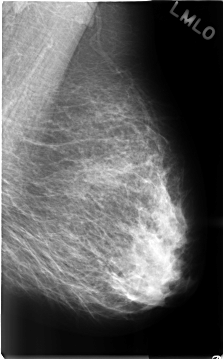

C_0313_1.LEFT_MLO

LEFT_MLO LINES 4664 PIXELS_PER_LINE 2896 BITS_PER_PIXEL 12 RESOLUTION 50 NON_OVERLAY